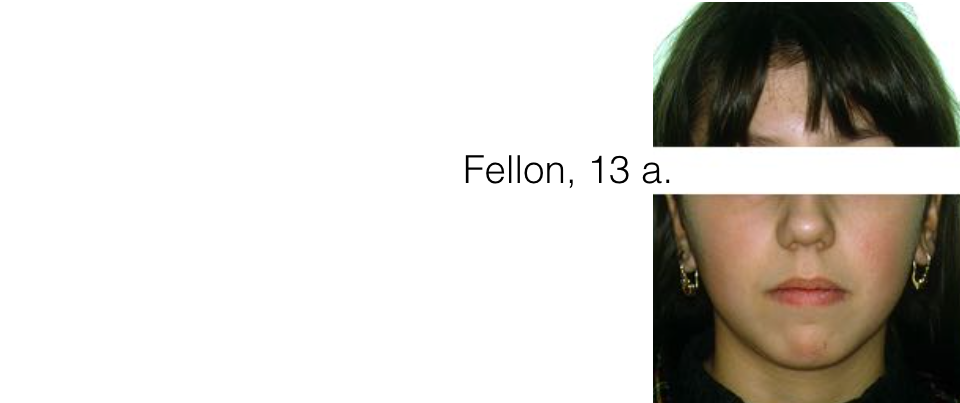

Nome

Fellon

Età

13